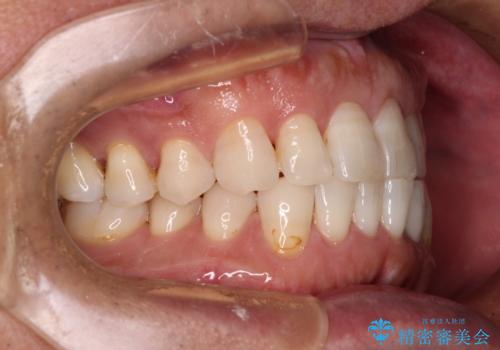

内側にある歯が干渉する 上顎前歯の部分矯正

- 上顎の前歯が内側にあり、下顎のセラミッククラウンと干渉することが気になるとのことで来院された患者様です。

上顎前歯にワイヤー装置を装着し、セラミッククラウンとは干渉しないようにしながら歯列を整えることとしました。

セラミッククラウンとの干渉はすぐに改善され、歯列も整いましたが、一方で、前歯で食事が噛みにくくなり、1年近い治療期間となりました。